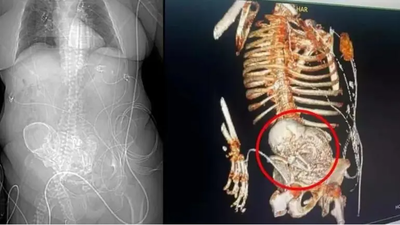

Una mujer brasileña con un feto calcificado desde hace 30 años muere en una operación Una mujer brasileña con un feto calcificado desde hace 30 años muere en una operación 21/03/2024